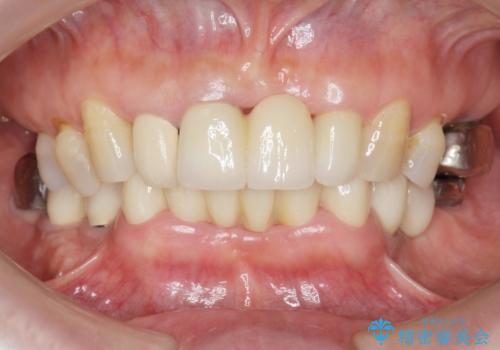

前歯が抜けそう ブリッジできれいに 70代女性

自然な仕上がりと使い心地に喜んで頂けました。

奥歯の治療もやりたいとおっしゃって下さり、今後進めていく予定です。